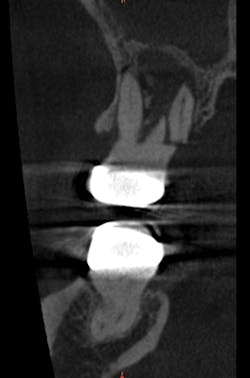

I acquired a post-extraction, small-field CBCT scan to evaluate the edentulous site for sinus health and bone height prior to sinus lift and simultaneous implant placement (fig. 3). Measurements from the crest of the alveolar ridge to the floor of the sinus were taken at the sites of the first and second molars, and were found to be 3.8 mm of bone height and 4.8 mm of bone height, respectively.

Figure 3: